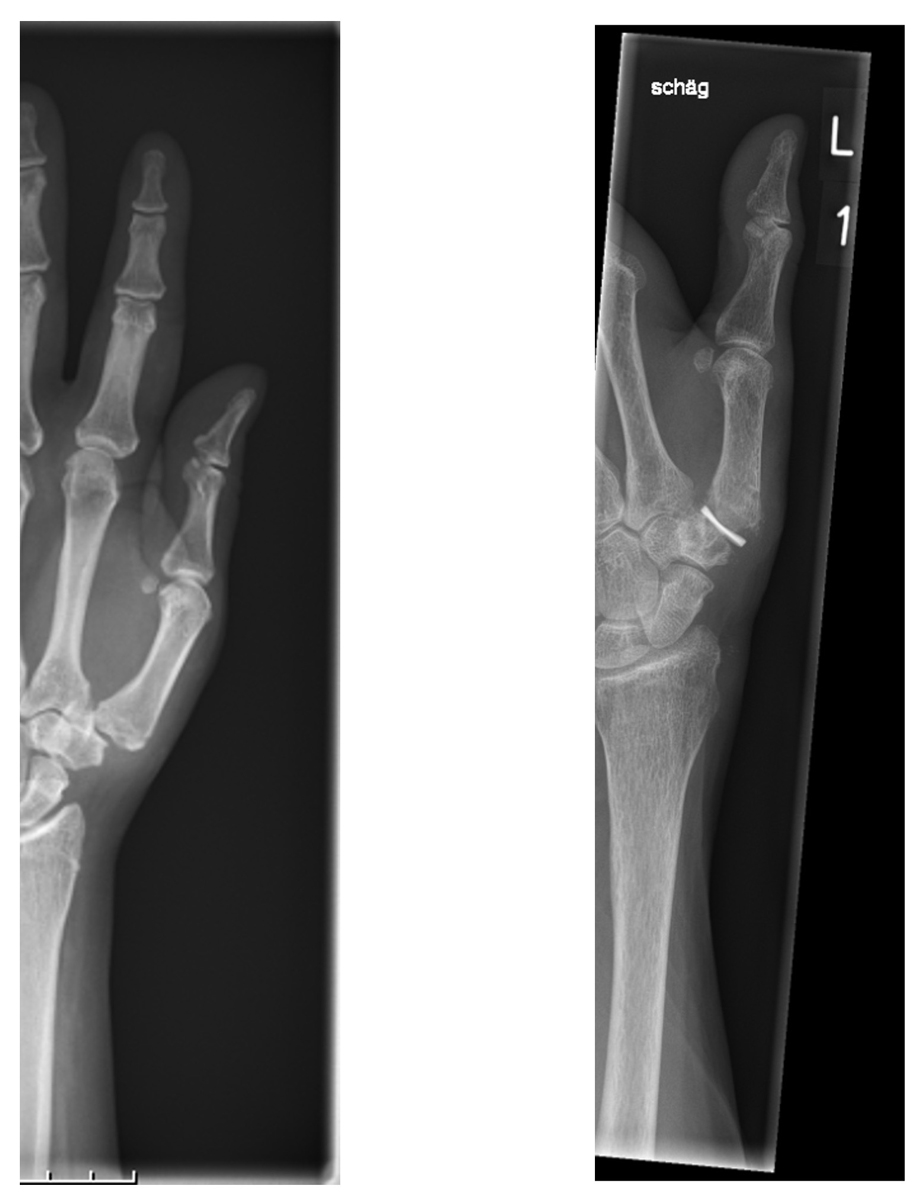

Pyrocarbon has a module of elasticity similar to that of cortical bone and is therefore well suited for interposition arthroplasties [73]. There are several implant models for different joints. The Pyrocardan® spacer is a hyperbolic paraboloid disk, which is inserted into the joint after partial resection of the first metacarpal and the trapezium bone (fig. 5). Five-year survival rates of 90% were reported [74]. In several studies, the Pyrocardan® spacer had similar outcomes to conventional arthroplasties, but shorter postoperative rehabilitation until relief of symptoms [75, 76]. Revision rates in several studies vary from 3.2% after 60 months of follow up to 25% after 26 months [75, 77].

Figure 5 Implantation of a Pyrocardan® spacer in the left thumb. Before (left) and after (right) implantation of Pyrocardan®. After partial resection of the trapezial and first metacarpal bone, the spacer of pyrocarbon is interposed in the joint.

The main benefit of using an interposition arthroplasty is the maintenance of length of the first ray. Furthermore, it can easily be revised by a trapeziectomy with or without LRTI in the case of failure [78, 79]. Pyrocardan® implants can also be used as a double arthroplasty in the TMC and STT joints in patients with stage IV osteoarthritis, or as an interposition spacer after failed trapeziectomy with subsidence [80]. As for the other prosthetic implants, no prospective long-term data proving its superiority to simple trapeziectomy are available and thus the potential advantages have to be outweighed with the complication rate and higher cost.